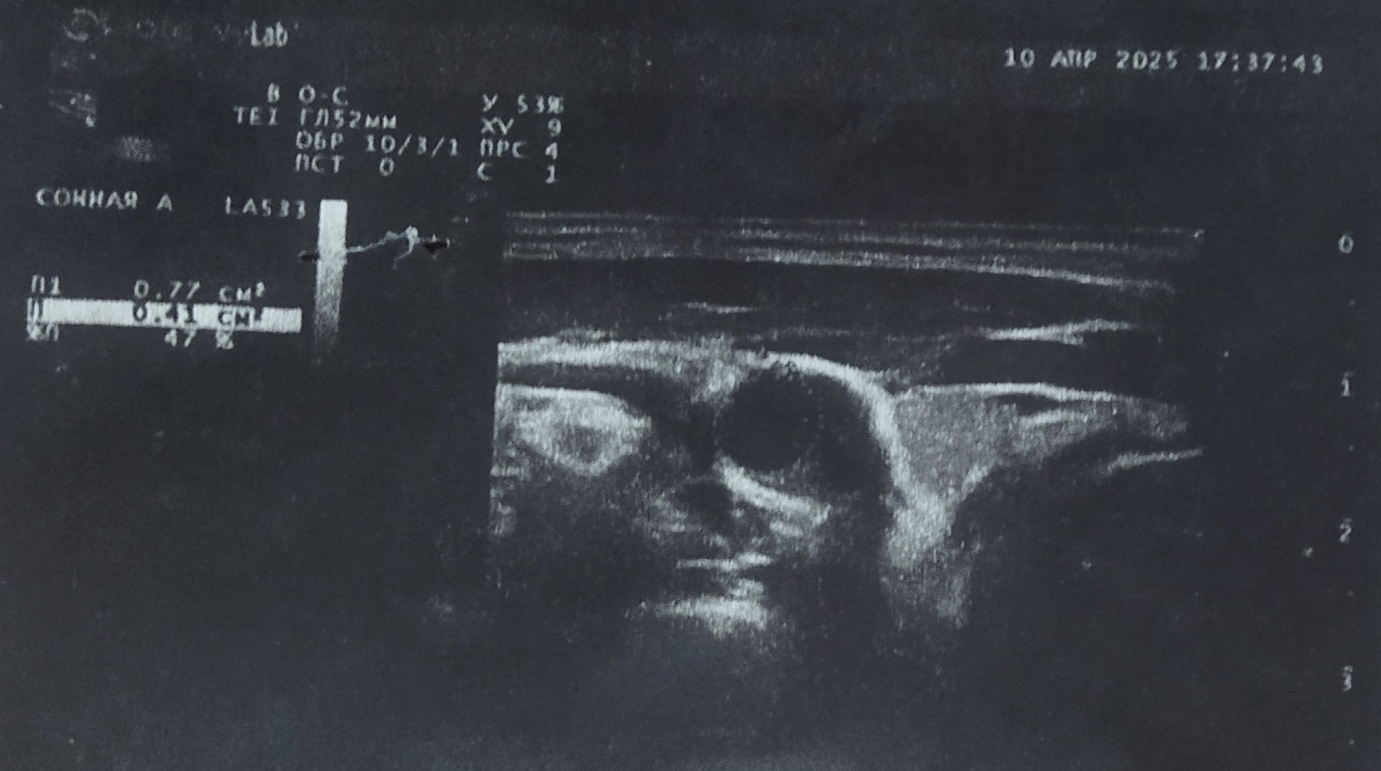

Проходил УЗИ сосудов шеи в Новосибирской больнице. Моя врач не могла понять что видит и пригласила ещё двух врачей. И начали они дисскусию, что же это может быть?

Есть ли тут специалисты, которые могу высказать свое профессиональное мнение?

Фото с распечатки